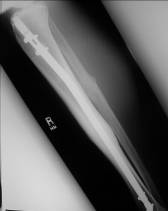

胫骨交锁髓内钉:

胫骨钉的适应症:

1、胫骨中1/3稳定型骨折:横形骨折、短斜形骨折、假关节。

2、胫骨中部60%长度内的不稳定性骨折:干骺端附近的骨折、长螺旋形骨折、节段性骨折、粉碎性骨折、骨折伴骨缺损。

胫骨钉的特点:

多用于胫骨中段骨折。尽管也可用于胫骨近端和远端骨折,但并发症发生率较高,易发生畸形愈合。